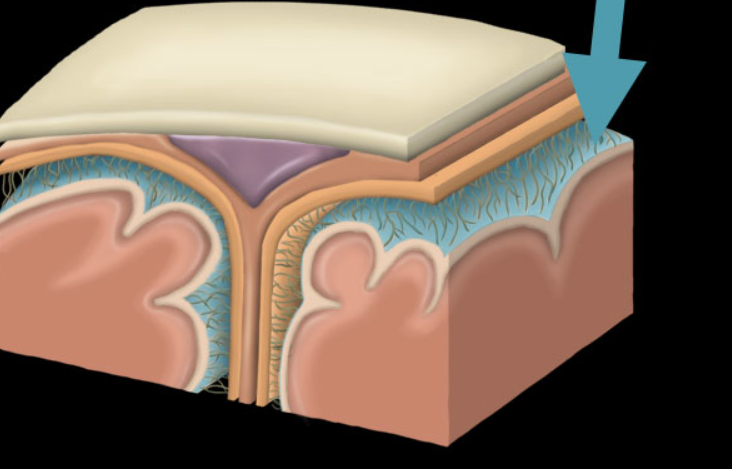

dura mater

arachnoid mater

Pia mater

dural sinus

choroid plexus